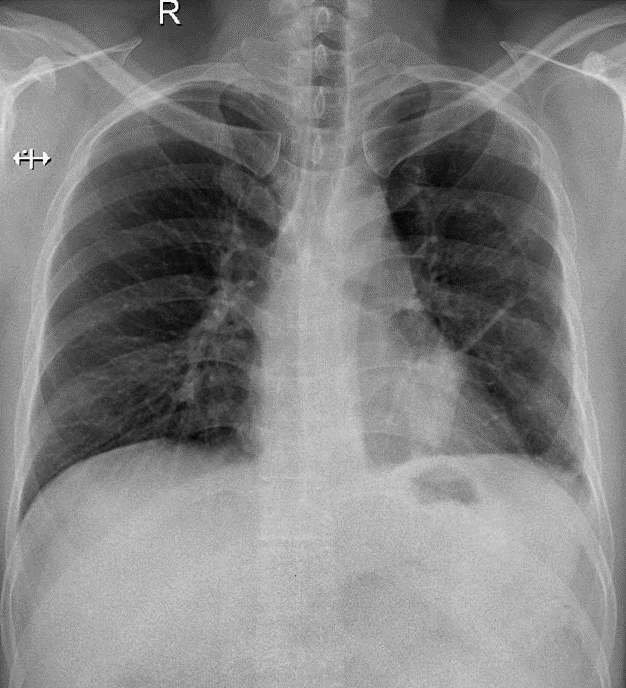

Hãy phân tích tình huống NAM 45 tuổi -CĐ:Theo dỏi K phế quản, tăng huyết áp

1-Xơ rải rác phổi (T) 2-U thùy dưới phổi (T)